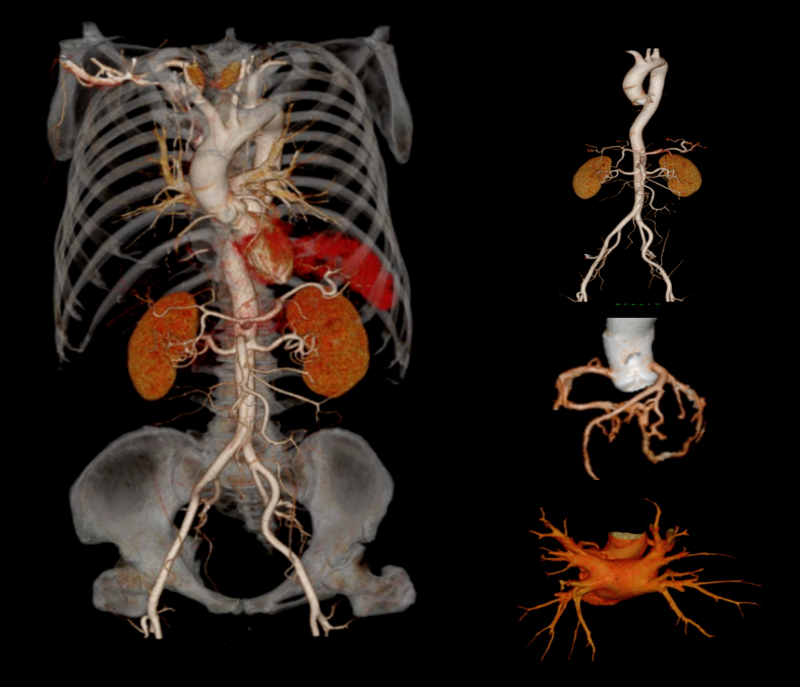

该设备集 “超高清成像、低剂量防护、极速扫描”于一体,将为辖区居民提供更精准、更安全、更便捷的诊断服务,标志着石岩人民医院在医学影像领域的诊疗水平迈入新阶段。 作为临床诊断的 “眼睛”,ANATOM X980的三大核心功能,直击患者就医痛点与临床诊断需求。 人性化设计与智能定位系统 ANATOM X980配备80厘米宽大机架孔径,结合舒缓氛围灯光,有效缓解患者检查时的紧张情绪。 设备搭载四块大尺寸高清触控屏,方便技师多角度掌握患者信息与设备状态,并可通过按键与无线遥控实现灵活摆位,大幅降低操作负荷,提升检查效率。 利用深度双目视觉认知系统,采用深度学习方式,赋予设备认知能力和行为,使系统能智能识别人体多个定位点,并在智能触屏终端上显示扫描部位,同时还能够自动识别拟扫描部位的等中心位置,实现精准化、智能化的患者摆位。 宽体探测器与极速扫描能力 依托16厘米宽体探测器结合0.25s的扫描速度,可实现全器官一站式扫描。 ▲ 心脏冠脉、主动脉、肺动脉联合扫描 通过AccuGating门控触发技术和 Adose mA电流调制技术和全新的算法、领先的AI成像技术手段,结合一键冠脉提取及分析、IVUS 模拟血管内超声、斑块分析、心功能分析、钙化积分分析、血管内窥镜、CT-FFR 技术,为患者带来了高成功率、高舒适度的单心跳(One-beat)心脏冠脉(CCTA)检查体验。 ▲ 心率103bpm 得益于一次单圈旋转最大16cm的覆盖范围,结合0.25s 的极快速度和安科独创的4D图像重建技术,在充分保证整个器官的各个位置数据的同时、同源、同向的条件下,实现了自由呼吸模式的肺部检查,为幼童、意识不清等患者肺部检查提供了最佳检查方式,为分析结果和治疗决策的准确性提供了保证。 高清影像与低剂量技术 ANATOM X980采用了基于深度学习技术的Artist 高保真图像降噪算法来对低剂量图像进行优化和处理。 与其他的算法相比,Artist 可以实现更彻底的噪声与图像信号分离,并确保在处理过程中图像细节信息不丢失,进而获得低剂量下高分辨的临床影像。 灌注扫描的剂量问题一直是临床中的老大难问题。ANATOM X980的超低mA采集及Artist还可在脑卒中解决方案中,可确保低剂量下获得精准的灌注数据。 此外,ANATOM X980还有其它几大独具特色的功能。 1.AI超分辨薄层重建技术(ASR) ANATOM X980搭载基于AI技术的高分辨率薄层图像重建技术(ASR=AI Super Resolution reconstruction),该技术利用神经网络处理单元通过深度学习的方式,对带有伪影的混叠投影数据进行伪影校正和重建,可显著降低混叠伪影,提高 CT 图像的分辨率,获得高分辨 0.3125mm 的超薄层图像,从而提高临床诊断准确性。 2.AccuImage 2048×2048显微成像 将图像数据量提高 16 倍,可显示和观察更多的病变影像细节。 3.AccuSpiral能谱成像 基于AI迭代重建与能谱解析技术,可定量分析组织成分,辅助肿瘤良恶性鉴别、结石成分分析及出血定位,为临床提供形态与功能融合的多维度信息。 目前,ANATOM X980 已在石岩人民医院影像科正式投入使用,从常规体检到复杂病症诊断,从成人检查到儿童诊疗,全方位满足临床需求。 石岩人民医院将以这台 “精准诊断利器” 为依托,持续提升诊疗能力,让居民在家门口即能享受到高质量医疗服务,用科技守护每一位居民的健康! 咨询电话 0755-27609000转0121 石岩人民医院放射科 石岩医院放射科现有医护42人,其中主任医师1名,副主任医师5名,中级职称24名,初级9名,助理技师、岗培各2名。 设备由数字化DR、CT、MR、DSA和骨密度仪等组成。中心设备齐全,拥有世界上先进的1.5T磁共振(MR)一台;螺旋CT3台(包括安科256排512层CT1台、安科64排128层CT1台、安科32排CT1台)。 数字减影血管造影机(DSA)1台;数字胃肠机1台;数字化DR和移动DR共6台;并配有现代化的PACS、HIS、肺结节和心脑血管AI辅助后处理诊断系统。 审核|梁雄 责编|马章林 审校|张永东 图文|郭文霞 编辑|冯丽萍 校对|吴曼莉